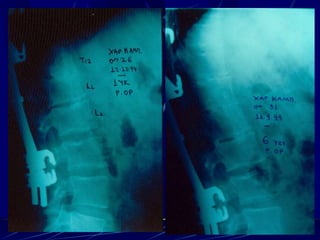

Φυματίωση της σπονδυλικής στήλης